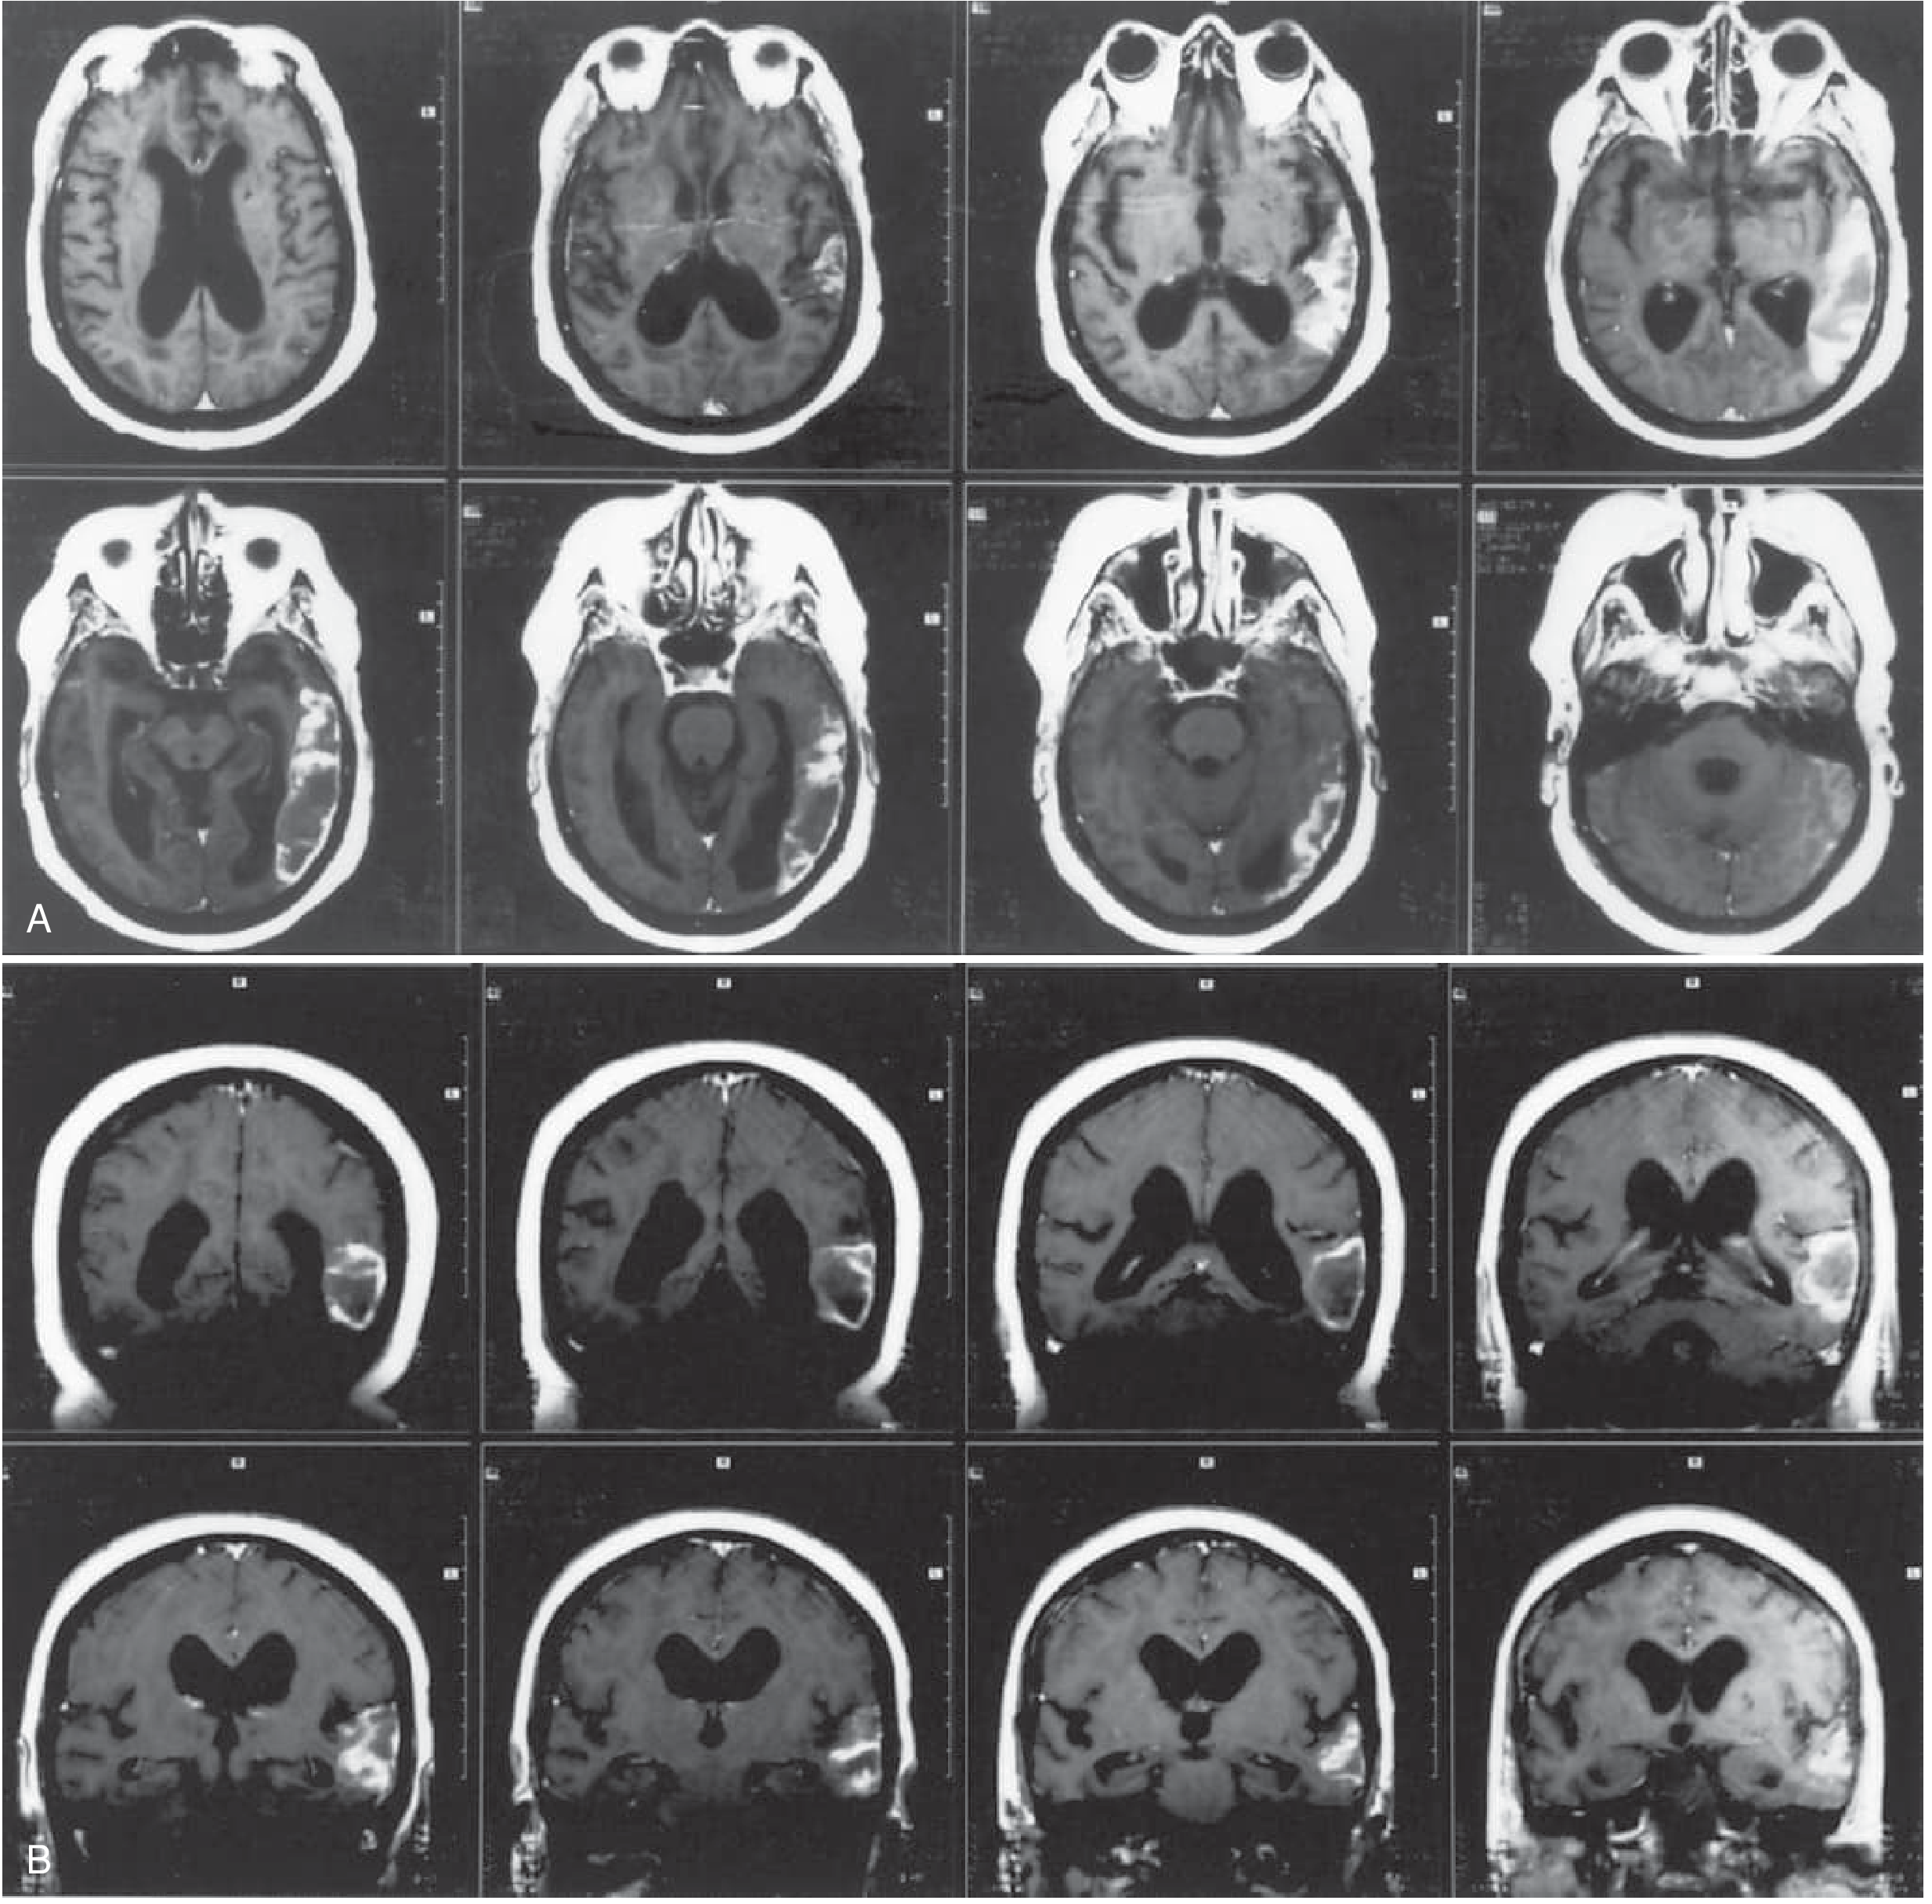

MRI scans from a patient with Broca's aphasia — left frontal infarction involving Broca's area, insula, and subcortical white matter. The patient made a good recovery.

MRI scans from a patient with Broca aphasia — infarction of the cortical Broca area, subcortical white matter, and insula — Bradley and Daroff's Neurology in Clinical Practice, p. 208